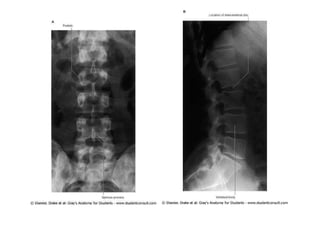

figura

08/12/2015 Dr. José Heitor M. Fernandes 263

Relação entre as raízes nervosas lombares e sacrais e os

corpos vertebrais lombares e sacros